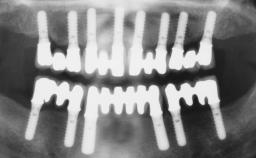

A fully edentulous 65-year-old woman was referred to our clinic for esthetic and functional dental rehabilitation. The patient presented with inadequate complete maxillary and mandibular prostheses, insufficient vertical dimension, and extensive tooth wear. The clinical examination and anamnesis showed no local or systemic contraindications, no signs or symptoms of bruxism, and an absence of smoking habits. The treatment proposed was implant placement in the mandibular interforaminal area and immediate loading with a fixed definitive prosthesis. A removable mucosa-supported complete prosthesis was indicated for the upper jaw, since its bone structure offered satisfactory retention and the financial condition of the patient disfavored a full-mouth implant-supported rehabilitation.

# of Implants 4

Type of Implants One-Piece

Defining Characteristics Fully edentulous lower jaw to be rehabilitated with two or more implants

Modality 3 or 4 interforaminal implants

Defining Characteristics Fully edentulous lower jaw to be rehabilitated with an implant-borne fixed dental prosthesis

Loading Protocol Immediate

Retention Screw-retained, with 4 or more splinted implants Screw-retained, with 4 or more splinted implants